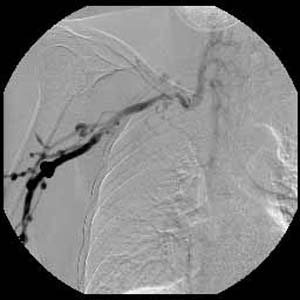

ÀÌÀü¿¡ °áÇÙ °ú°Å·Â ÀÖ´Â ³²ÀÚ 41¼¼·Î CXR ÀÌ»ó ¼Ò°ßÀ¸·Î refer